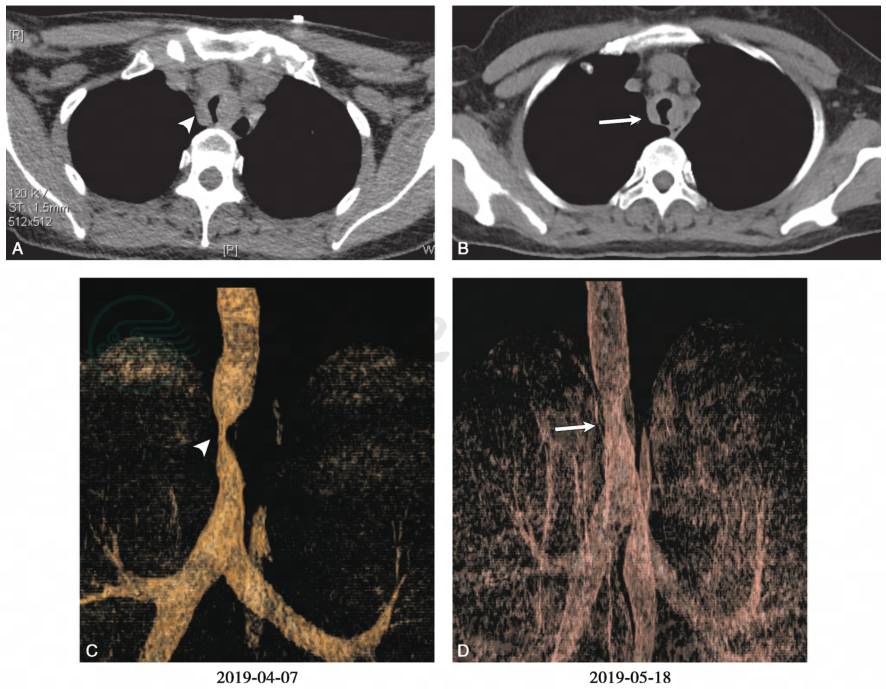

患者院外口服激素1个月,自觉喘憋症状明显改善。2019年5月18日复查肺功能示:通气功能障碍明显好转(图6)。复查胸部CT增强+气道三维重建示:气道狭窄明显好转(图7)。患者目前逐渐减量口服甲泼尼龙片,门诊定期随访。

图7 治疗1个月后复查胸部CT增强+气道三维重建示:治疗后(白箭)主气道狭窄较治疗前(箭头)明显好转

引自:主编:.呼吸与危重症医学疑难与危重病例精选.第1版.ISBN:978-7-117-30147-3